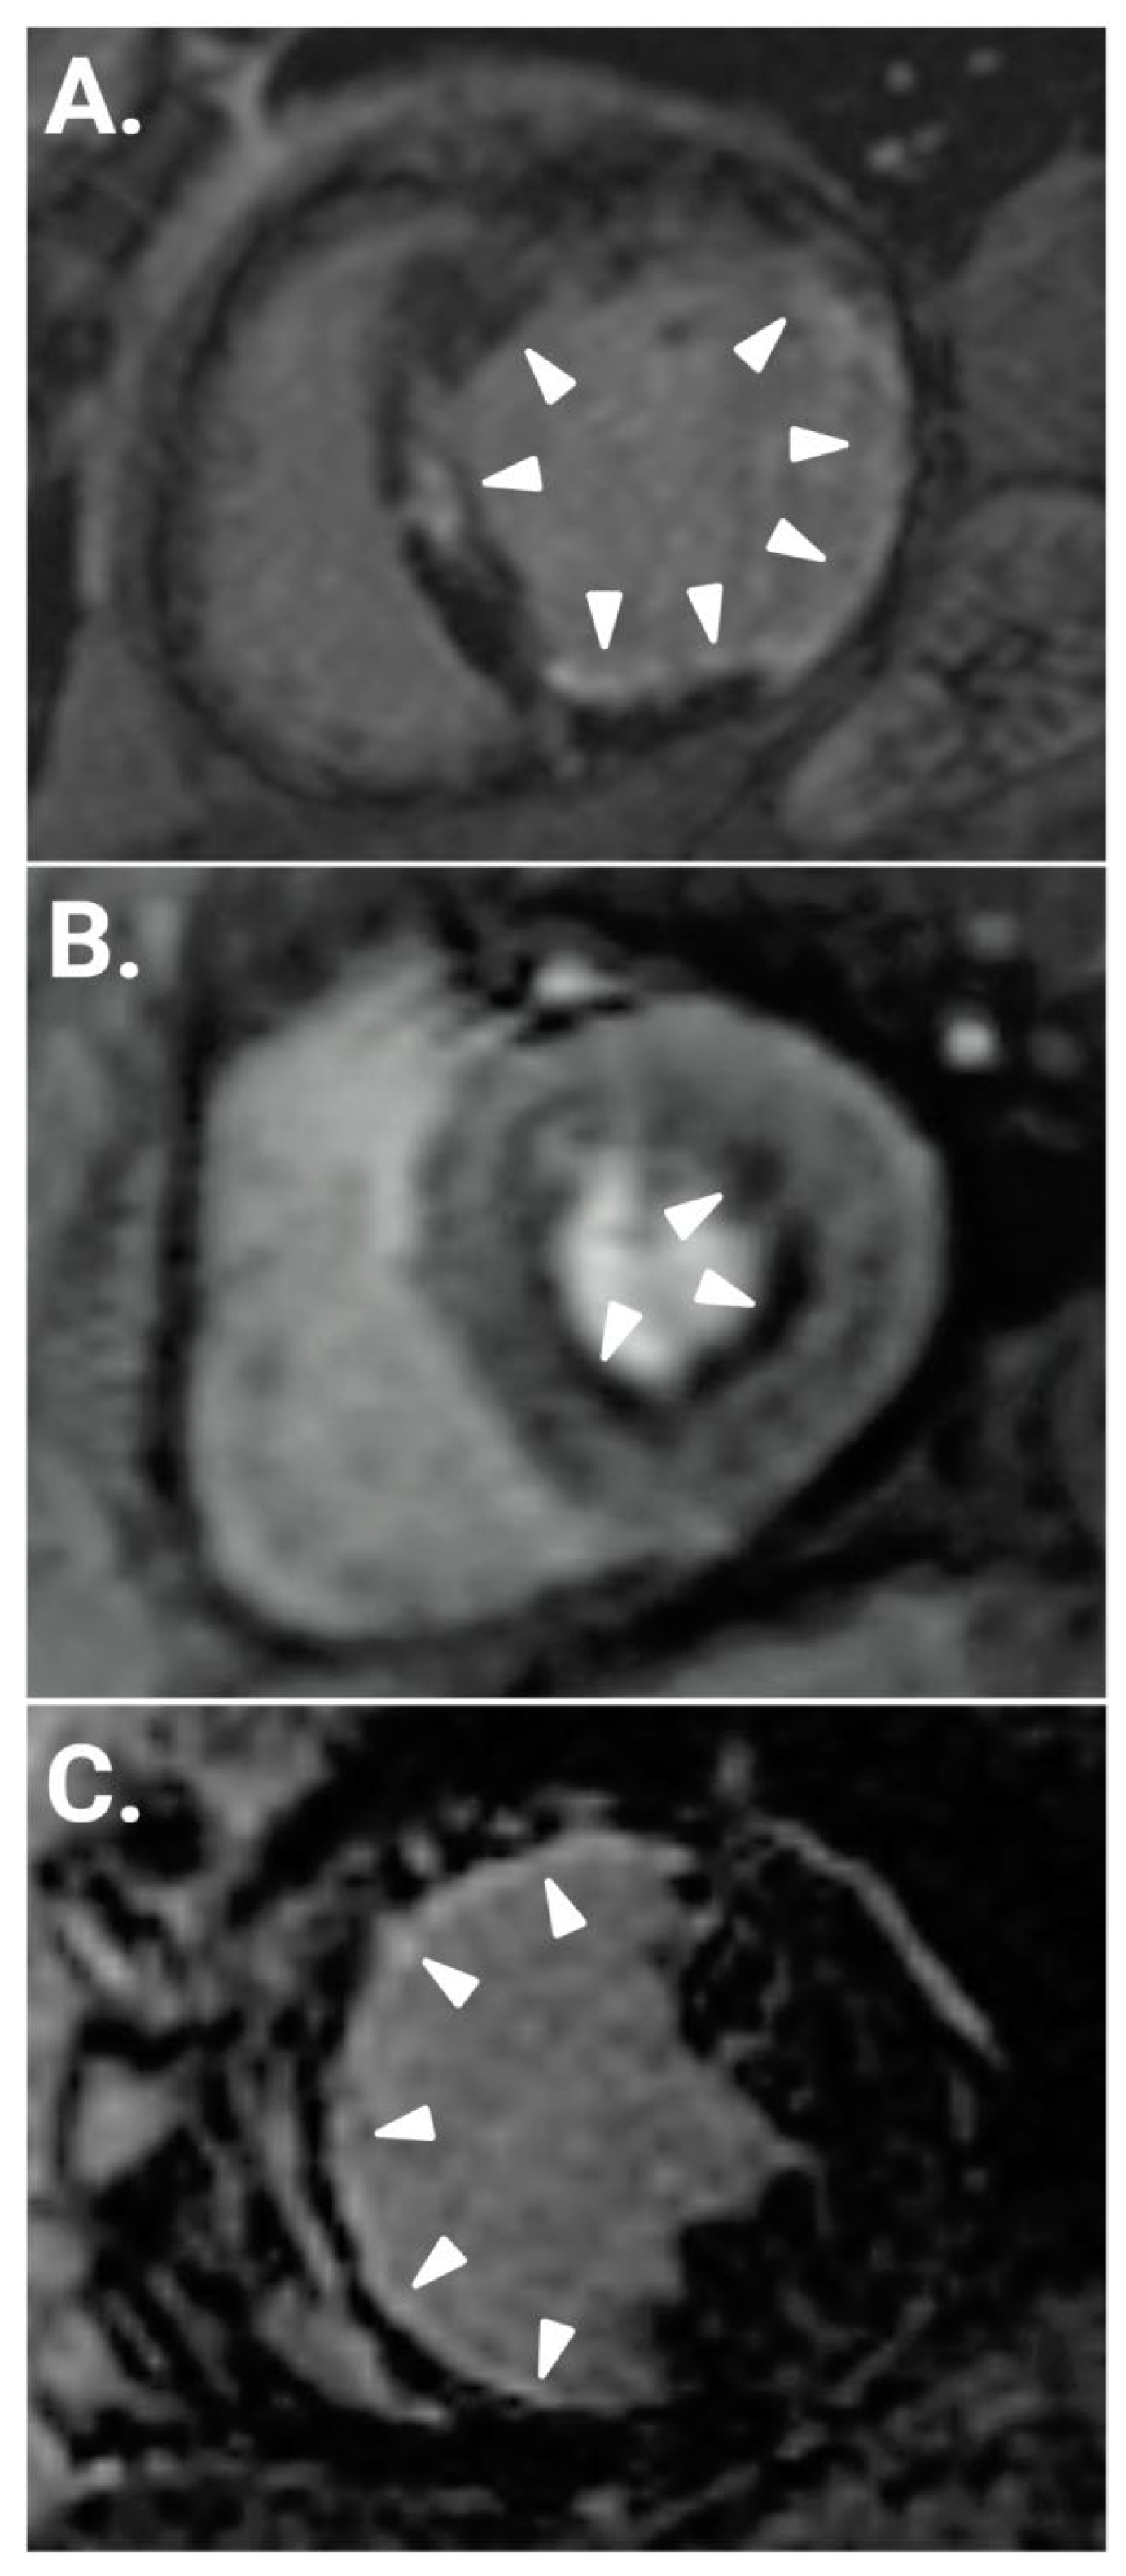

- T1-weighted (T1-W) Images and Late Gadolinium Enhancement (LGE)

- Kwong, R.Y.; Sattar, H.; Wu, H.; Vorobiof, G.; Gandla, V.; Steel, K.; Siu, S.; Brown, K.A. Incidence and prognostic implication of unrecognized myocardial scar characterized by cardiac magnetic resonance in diabetic patients without clinical evidence of myocardial infarction. Circulation 2008, 118, 1011–1120. [Google Scholar] [CrossRef]